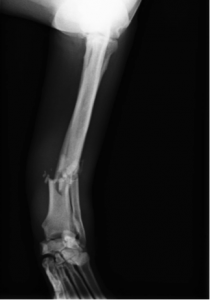

術前レントゲン

コメント;

撓尺骨遠位1/3での粉砕骨折であり、かつ遠位の骨片は粉砕骨折の安定に必要なスクリューの数を確保するのが困難なほど短いものであった。また、遠位には亀裂の存在も示唆された。